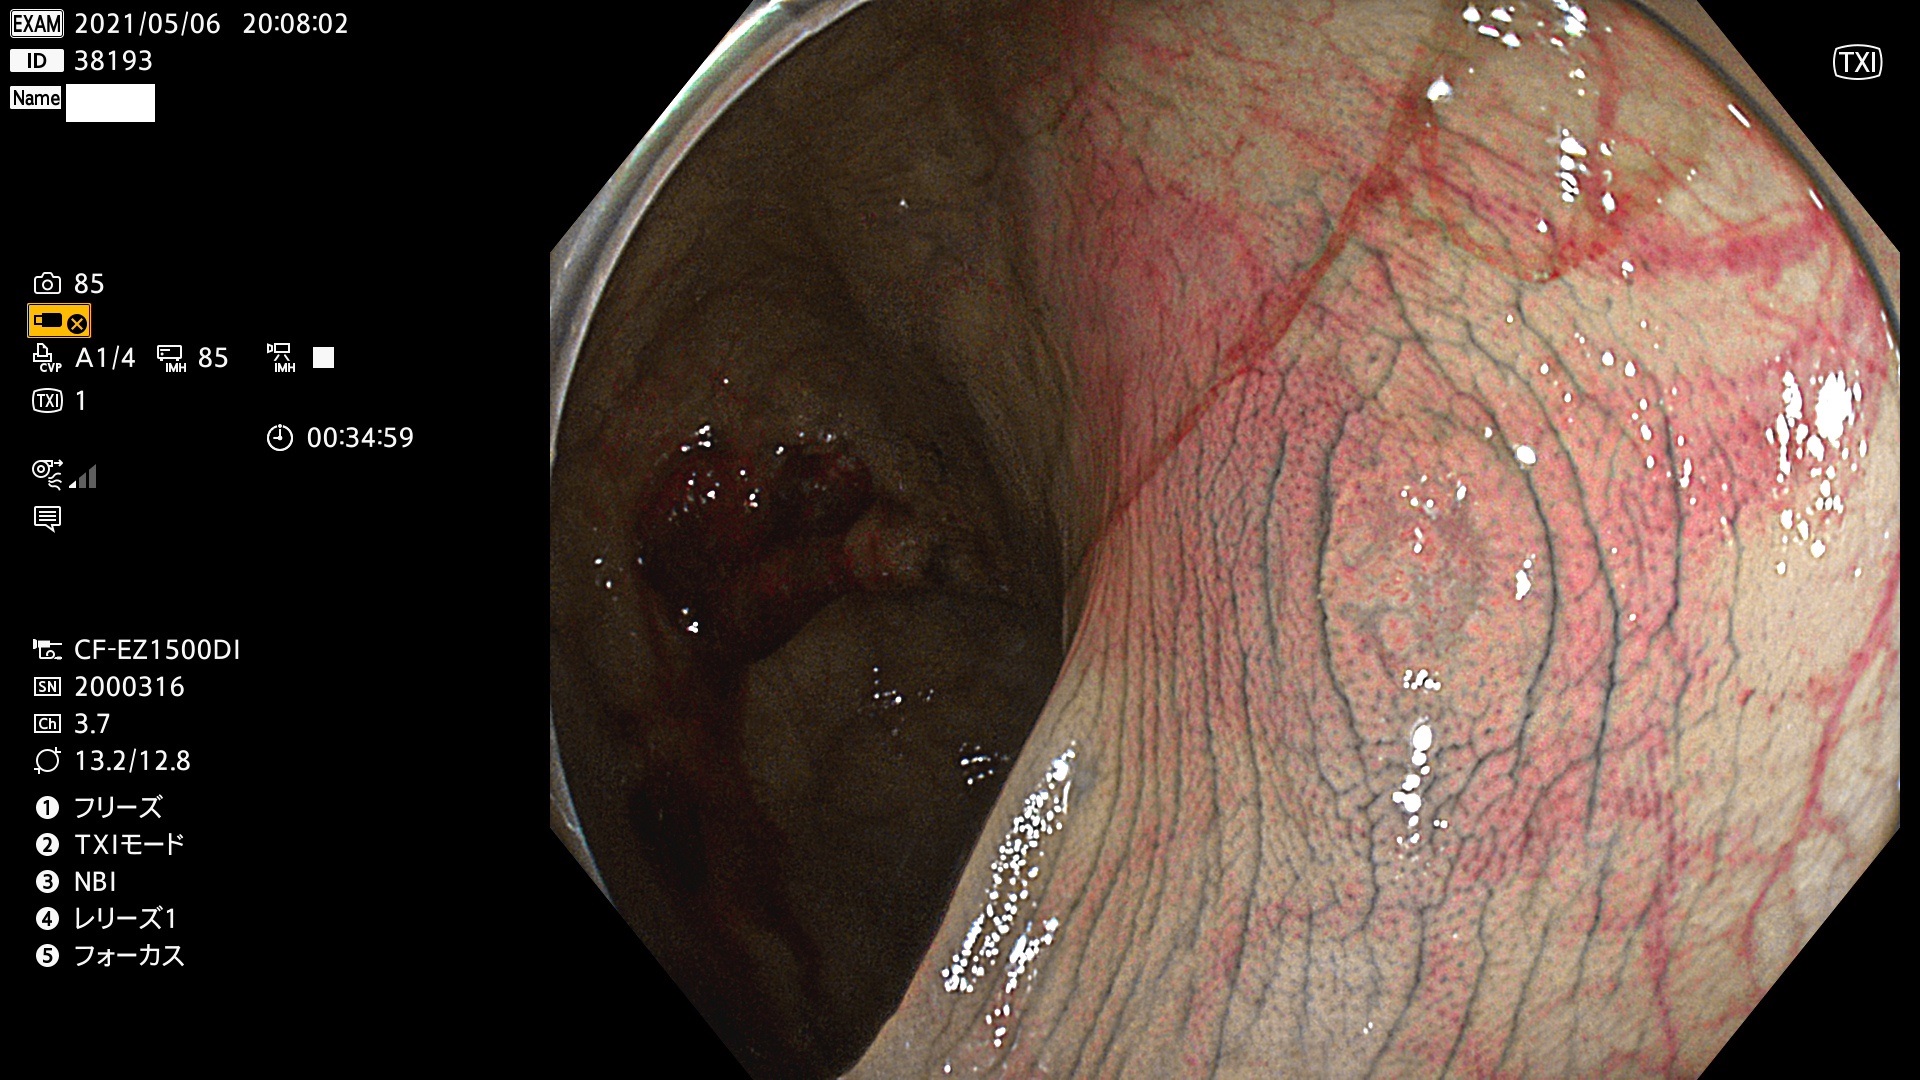

腺腫発見率 72 % (カルテ番号 38100〜38199の100名の方の検査結果で集計)大腸癌検診最新情報

以下のカルテ番号の方に腺腫(Adenoma,Group3〜5)が見つかりました(集計法)

38101 38103 38104 38106 38107 38108 38109 38110 38111 38112 38113 38114 38115 38117 38118 38122 38123 38124 38125 38126 38127 38128 38130 38131 38132 38135 38137 38138 38140 38141 38142(SSAPのみ) 38143 38144 38145 38146 38147 38148 38149 38150 38151 38152 38153 38154 38157 38158 38160 38161 38162 38164 38165 38166 38167 38168 38169 38172 38176 38177 38178 38181 38182 38183 38184 38187 38189 38190 38191 38192 38193 38194 38195 38196(SSAPのみ) 38198

発見困難で危険性の高い平坦型病変(上記100名より抽出) ![]()